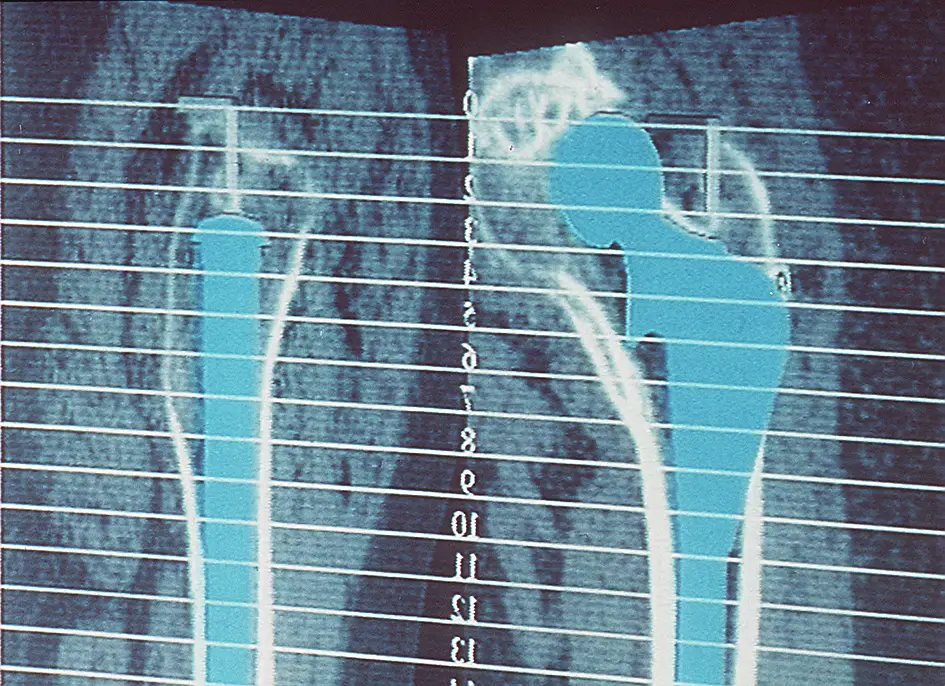

Das vorgestellte System CASPAR ist unseres Erachtens im Einsatzgebiet in hervorragender

hervorragende dreidimensionale Planungsstation, die es uns ermöglicht, durch eine

computertomographische Röntgenuntersuchung eine 3 D- Darstellung es gesamten

Hüftgelenkes auf dem PC dem Operateur zur Verfügung zu stellen. Die Strahlenbelastung

Die computergestützte Operationsplanung erlaubt nach Durchführen einer

computertomographischen Untersuchung der Oberschenkelbeckenregion die dreidimensionale

Implantation eines ausgewählten Hüftschaftimplantates in den individuellen Knochen des

Patienten. Hierbei können sowohl die jeweiligen Rotationsstellung des Schenkelhalses, wie

auch die individuelle Dimensionierung des Oberschenkelschaftes berücksichtigt werden.

Durch das Auflösen in zahlreiche Querschnittsbilder kann der Sitz des Implantates über

seine gesamte Länge räumlich kontrolliert werden. Die exakte Größenauswahl und

Positionierung des Schaftimplantates ist somit möglich, in einer Form wie es

intraoperativ in dieser Präzision von Hand nicht durchgeführt werden kann, da

selbstverständlich nicht der gesamte Oberschenkelknochen freigelegt werden kann.